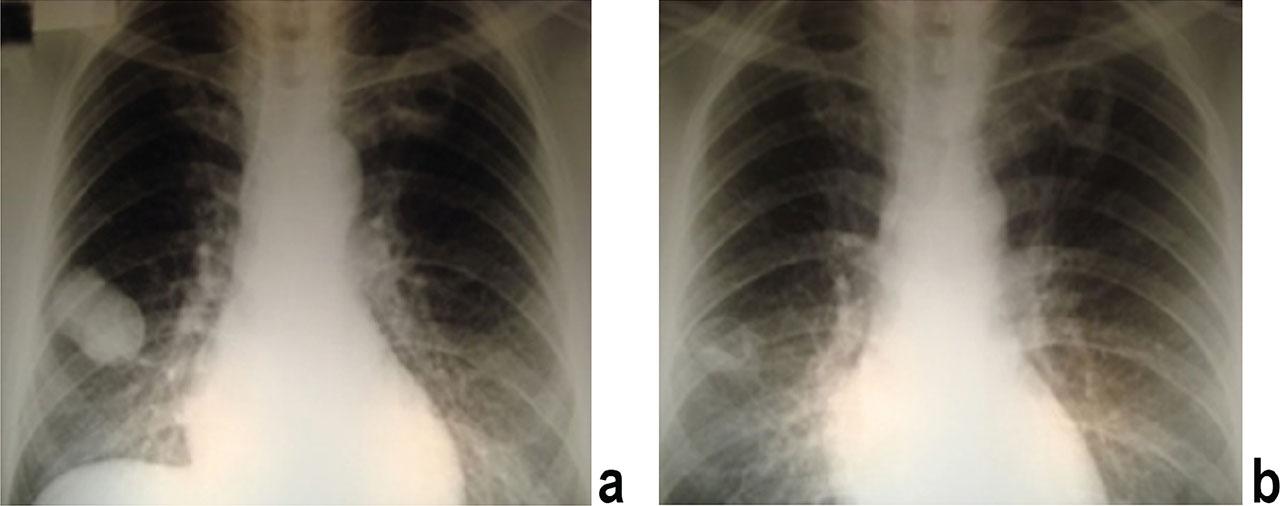

Two (13.3 %) out of 15 pulmonary cysts failed to respond to treatment with albendazole and praziquantel given for four months. They were in one patient and their sizes were 40 mm and 45 mm in diameter. Nine (60 %) of the pulmonary cysts reduced their sizes with more than 50 % along with degeneration of the cyst contents and 4 (26.7 %) cysts disappeared (Fig. 3).

Pulmonary hydatid cysts a) before treatment b) after 3 months combination therapy.